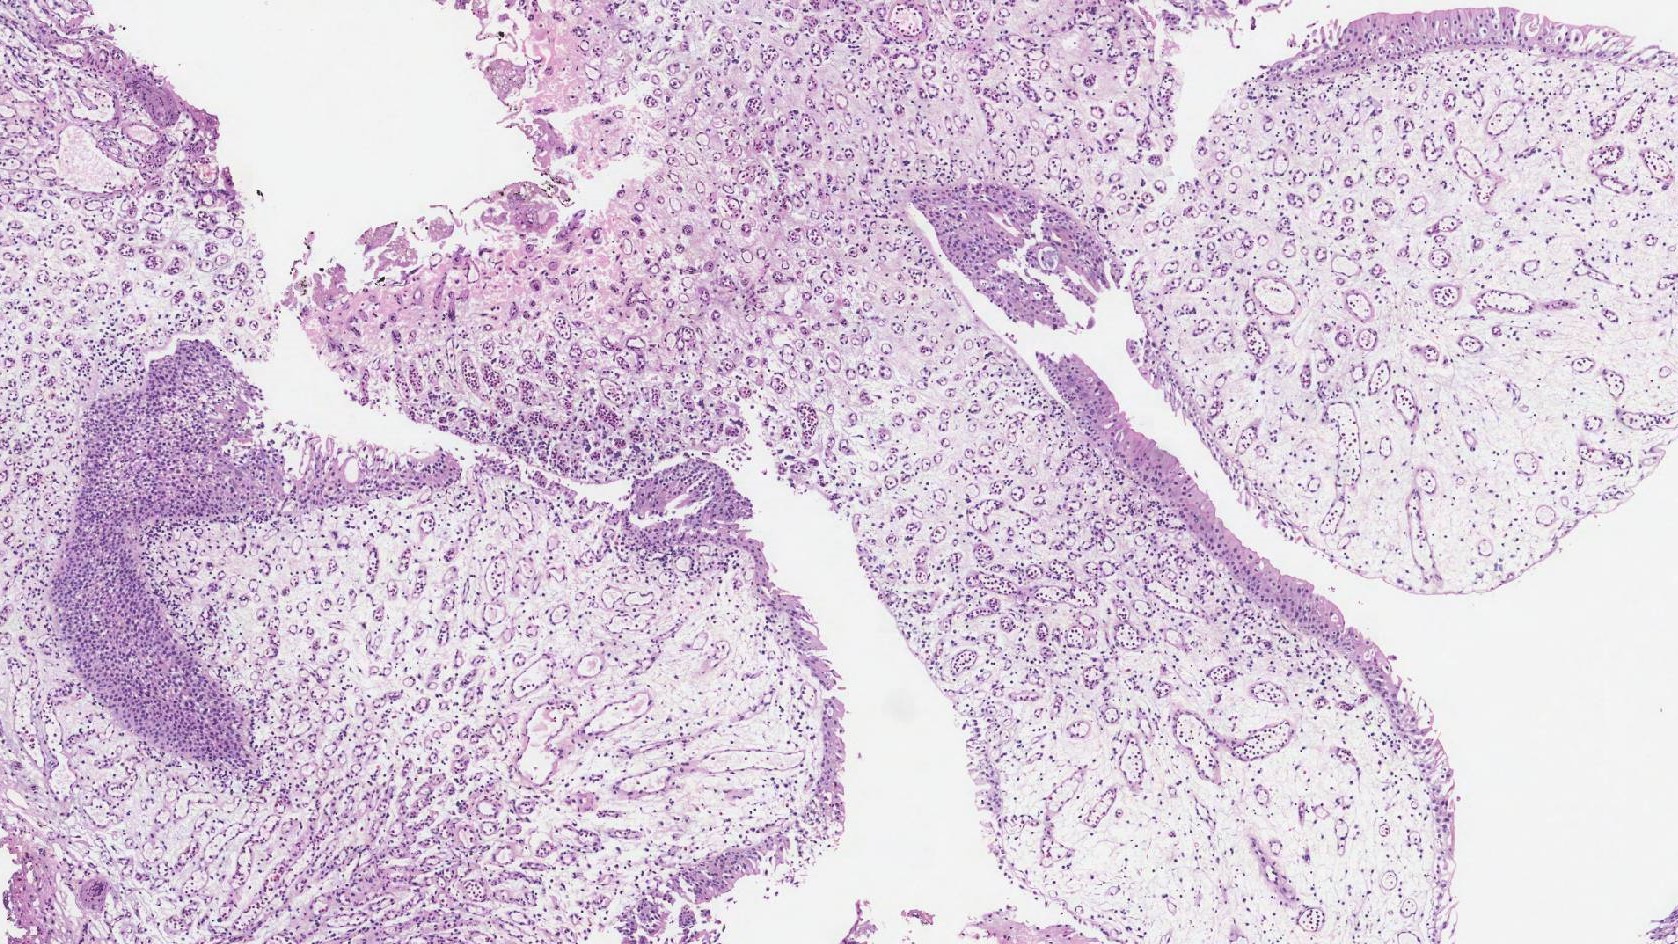

膀胱ポリープは、膀胱の内層から突き出た小さな、多くの場合カリフラワーのような増殖物です。

膀胱ポリープ内の細胞は異常です。細胞に異常があっても、必ずしも癌性であるとは限りません。

膀胱ポリープは良性である可能性があり、異常な細胞は無害であることを意味します。良性の腫瘍や腫瘍は転移しません。つまり、体内の他の組織や器官に広がります。膀胱内の良性腫瘍は通常、生命を脅かすものではありません。

しかし、膀胱ポリープは癌性になる可能性もあります。また、膀胱内の癌性増殖は、尿路の他の領域または近くの組織に広がる可能性があります。